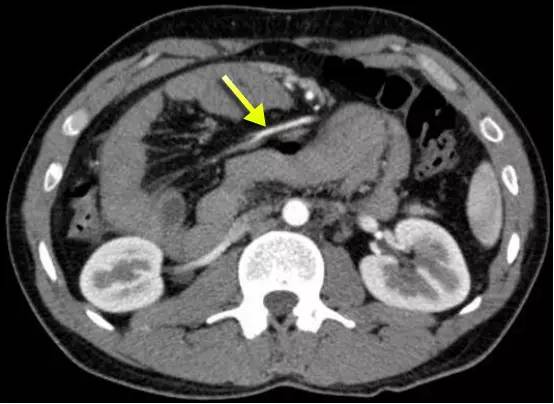

下图:右侧十二指肠旁疝,疝囊位于肠系膜主干的右侧,肠系膜的空肠支(黄箭)环绕至肠系膜上动脉主干的右后方为其供血。